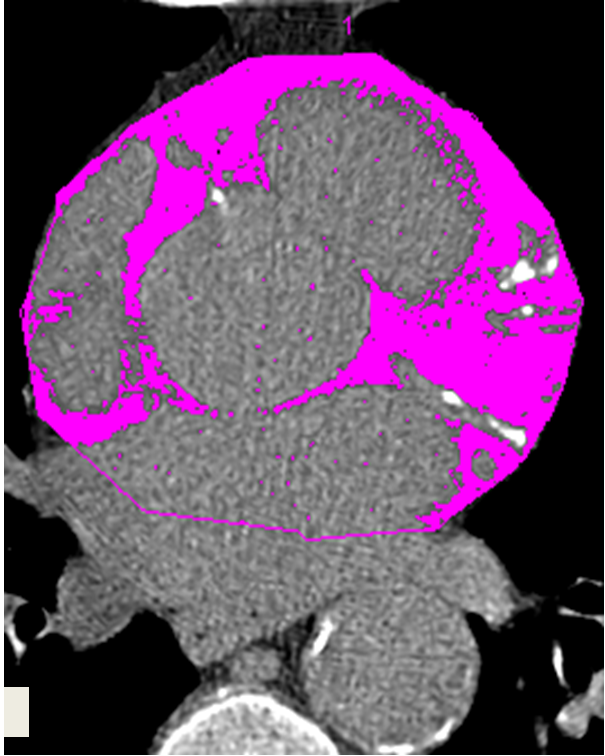

International cardiac research led by a University of Alberta medical scientist shows fat deposits around the heart - that can be spotted via simple CT scans - are a solution to help predict death in chronic kidney disease patients. But the test isn't common clinical practice in Western Canada, says lead researcher Paolo Raggi.

"We wanted to know if this type of heart fat is related to poor outcomes for patients with chronic kidney disease, and it was a very clear marker of risk," says Raggi, a researcher with the Faculty of Medicine & Dentistry at the U of A and the academic director of the Mazankowski Alberta Heart Institute. "The greater the amount of fat around the heart, the greater the mortality rates were in patients."

His team examined CT scan results from 109 U.S. patients with chronic kidney disease from a randomized, clinical trial and discovered that as the volume of fat around the heart increased, so did the risk of death. For every 10 cubic centimetre increase in heart fat, the risk of death rose six per cent, notes the article. Patients with higher than average amounts of heart fat had five-year survival rates of about 45 per cent - markedly lower than the 71 per cent survival rate for patients with lower than average amounts of heart fat.

The article notes that chronic kidney disease patients do not usually receive CT heart scans. The authors recommend that clinical practice should include CT scans for these patients in the future with notes made on the test results about the amount of heart fat found.

"This is a new marker physicians can use for chronic kidney disease patients," says Raggi. "It's very easily implemented, and costs little. Currently, it's not used often enough in this part of Canada and physicians should have a more flexible approach to consider looking for this marker, which can be used to quickly estimate risk for their patients. Don't just look for calcium buildup in the arteries, look for fat volumes in the heart too."